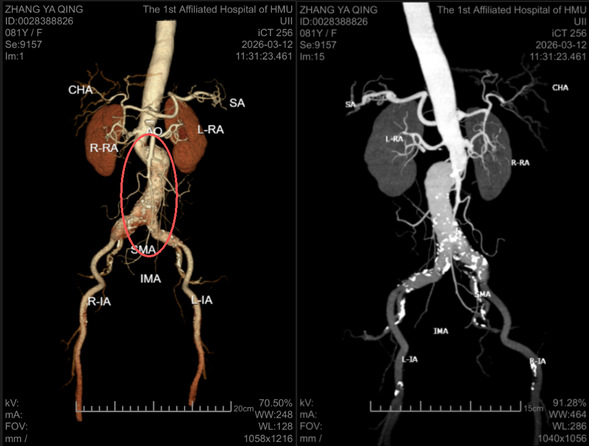

近日,81岁高龄的张大娘在我院血管外科顺利“拆除”了一枚藏于腹中的“隐形炸弹”。张大娘此前在外院住院期间,通过检查意外发现腹主动脉瘤伴偏心性扩张,并伴有髂动脉扩张。所幸,她曾看到我院去年发布的相关科普,意识到问题的严重性,于是专程来到我院血管外科寻求进一步诊治。

入院后,我院血管外科李喜春主任团队为张大娘进行了全面评估。考虑到患者高龄、病变位置复杂,团队为其量身定制了“右髂内动脉栓塞+腹主动脉+双侧髂动脉一体支架置入术”的个体化微创方案。

主髂动脉瘤扩张区域

入院第三天,手术顺利实施,术后恢复良好,入院一周便康复出院。这一案例,再次印证了主髂动脉瘤只要及时发现、规范治疗,完全能够取得良好预后。